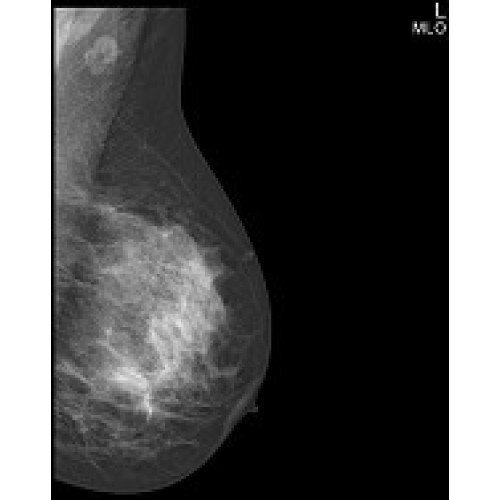

IMS GIOTTO IMAGE 3D

Современная маммографическая система с технологией томосинтеза для точной трехмерной визуализации. Обеспечивает высокое качество изображения при минимальной лучевой нагрузке. Подходит для скрининговых программ и углубленной диагностики. Интегрируется с медицинскими информационными системами.

Маммограф IMS GIOTTO IMAGE 3D – инновационная система для ранней диагностики заболеваний молочной железы с технологией томосинтеза. Аппарат сочетает высокое качество изображения с минимальной лучевой нагрузкой, что делает его идеальным решением для современных медицинских учреждений.

• Технология цифрового томосинтеза для трехмерной визуализации тканей

• Полноценная 2D и 3D маммография в одном исследовании

• Режим DBT (Digital Breast Tomosynthesis) для послойного анализа